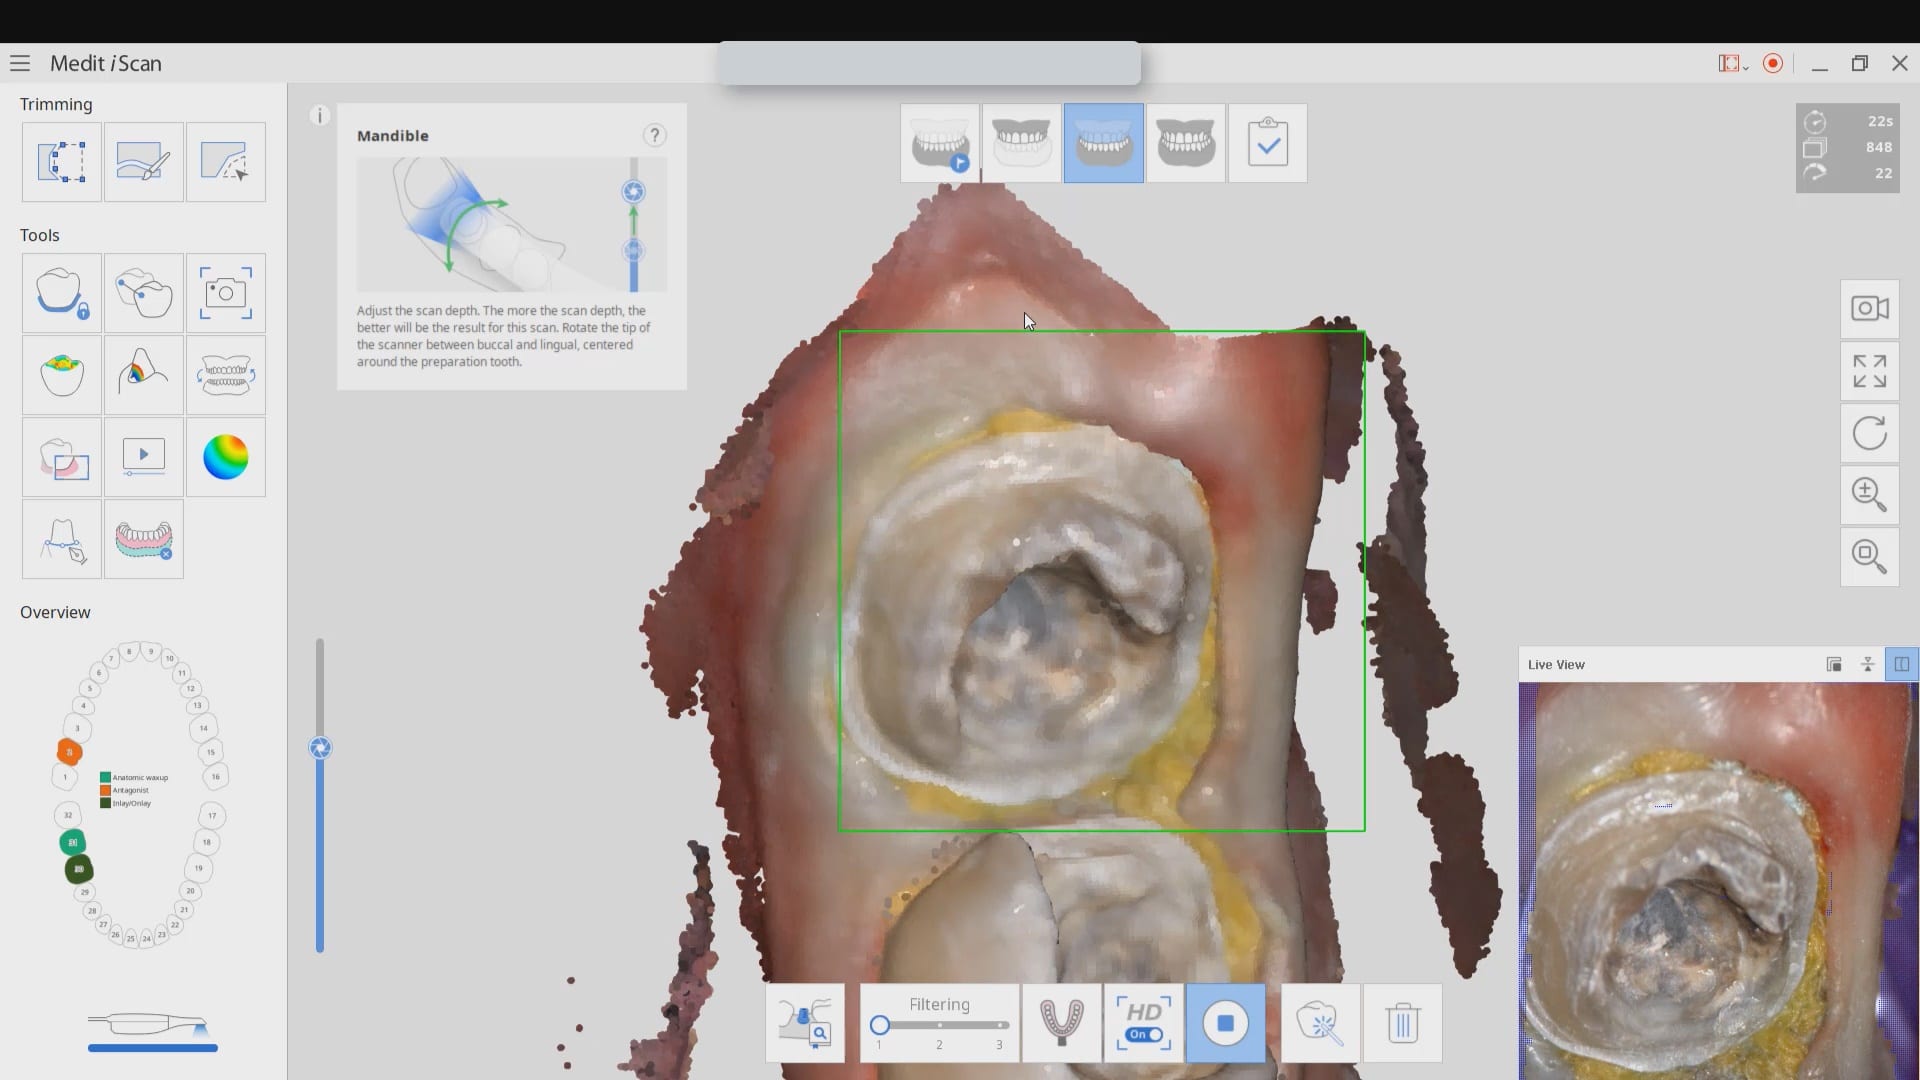

Exposing and Correcting the Distal Margin Scan

In this video we demonstrate some of the most common problems associated with second molar impressions. Usually the distal margins can be blurred by the presence of hemorrhaging or soft tissue. In this particular case, we use the tip of the camera to displace the tissue and digitall correct an area for better accuracy. The isolite systemisolite systemisolite system does a great job controlling the tongue and the lips and with proper retraction you can image a quadrant in very little time